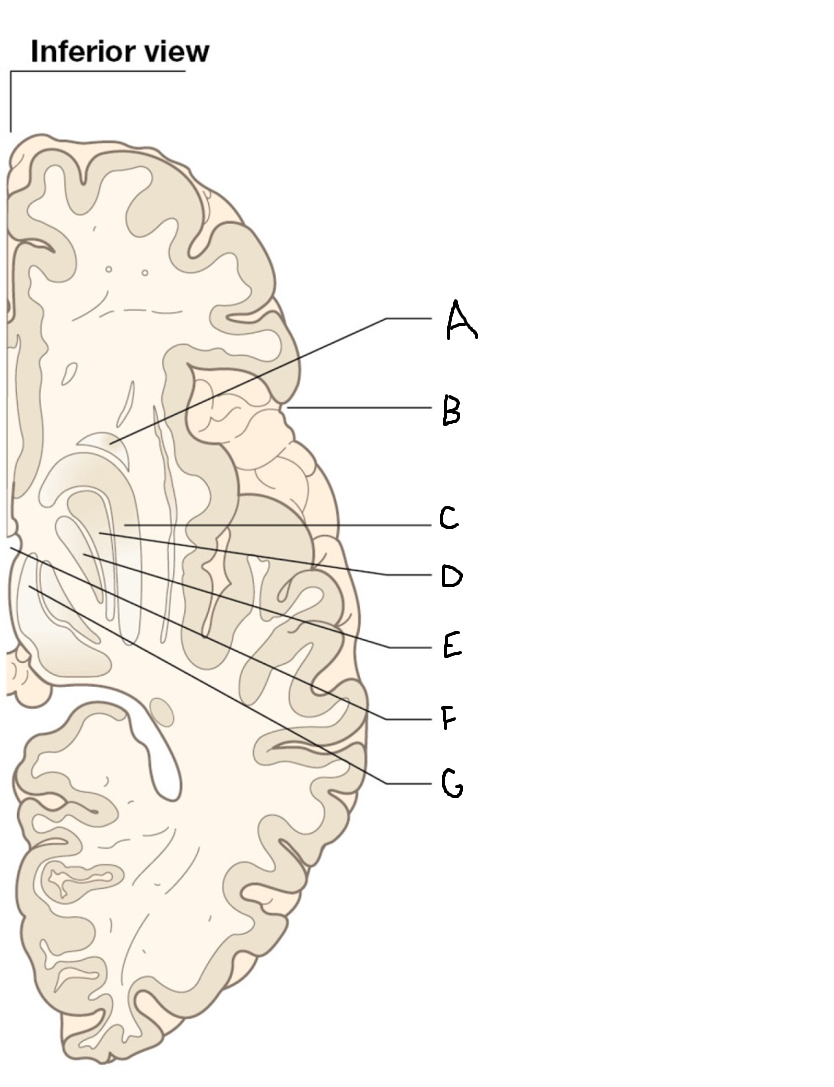

A

internal capsule (anterior limb)

B

caudate nucleus body

C

caudate nucleus head

D

putamen

E

caudate nucleus tail

F

thalamus

G

internal capsule (posterior limb)